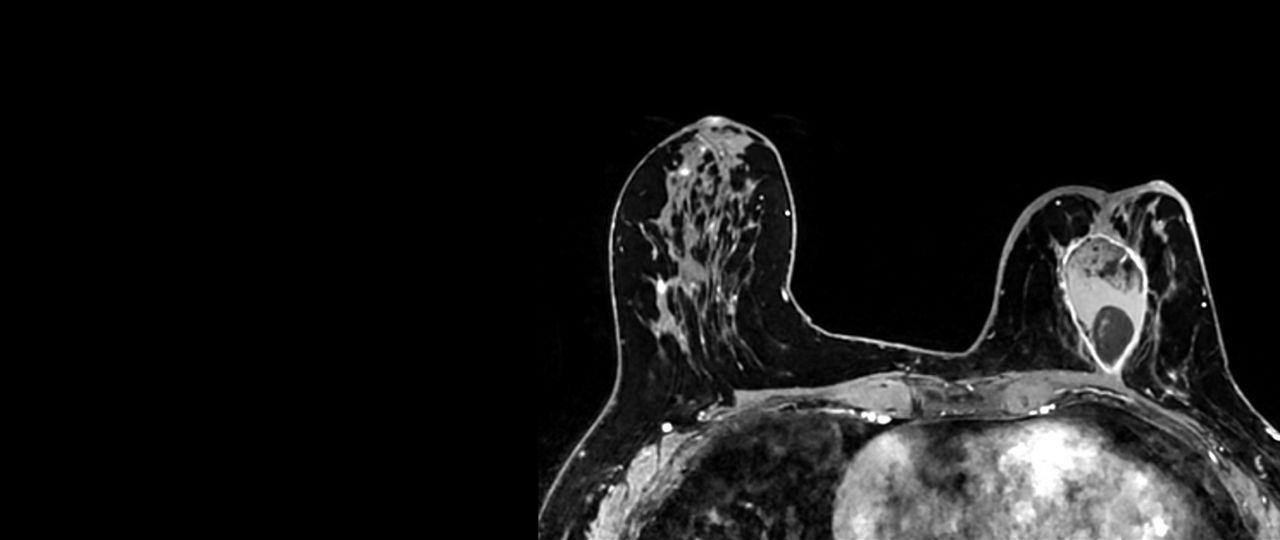

Precision and personalization

Vibrant-and-VibrantFlex1040-x-585

Read case study ico-caret-right